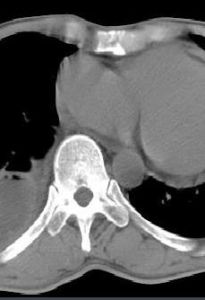

影像學表現在影像學X線切線位片上,包裹性積液表現為自胸壁向肺野突出之半圓形或扁丘狀陰影,其上下緣與胸壁的夾角呈鈍角,密度均勻,邊緣清楚,常見於結核。治療結合X線或超音波定位在特定部位進行穿刺,抽吸積液或注入藥物。